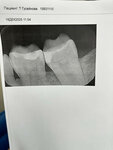

Лечение кариеса превратило живой зуб в постоянную боль. В ноябре 2025 обратилась в эту сеть клиник , где столкнулась с непрофессионализмом и отписками! Хронология ада: 1. 19.11.25 — Врач Пермякова Ю.В. лечит кариес на 37 зубе. Зуб ДО этого не болел. 2. 01.12.25 — Первая коррекция (зуб болит при жевании). Больно, анестезии нет. 3. 08.12.25 — Вторая коррекция + покрытие лаком (боль при чистке щеткой). Больно, анестезии нет. 4. 18.12.25 — После скандала (звонок за 30 мин до приема, что лечить не будут) попадаю к врачу Федоровой Е.К. (Радищева, 25). Оказывается, Пермякова лечила зуб, который уже был запломбирован год назад в этой же сети! Врач Федорова делает рентген (пломба до каналов далеко, пульпита нет) и полностью перелечивает зуб. Документы выдать отказались. Боль не прошла. 5. 23.12.25 — Коррекция у Федоровой + лак. Диагноз «пульпит» ставят предположительно. Клиника не выдала мне документы ни после одного приема, игнорируя мои заявления. Позже я всё же получила выписку, но это просто хронология без печатей, подписей и деталей — формальная отписка. При этом в ответ моей страховой клиника нагло врёт, что всё сделано корректно и документы выданы в полном порядке. Итог: Зуб болит до сих пор (уже 4 месяца). Теперь по их вине мне предстоит удалять нерв и ставить коронку за свои деньги. Клиника скрывает правду, выдаёт неполные документы и перекладывает вину на пациента. Вывод: Врач Пермякова либо «лечила» несуществующий кариес, либо сделала это настолько грубо, что убила здоровый зуб. Прикладываю скрины отписки в мою страховую и фото рентгена зуба сделанного 18.12.25 у них же. UPD от 11.05.26: Мне вылечили зуб в другой клинике, поэтому всё, что вы тут написали - это просто оправдание вашей некомпетентности. Если вам интересны подробности, я могу сообщить. Но вы верно заметили, что доверие к вам подорвано. Кстати, забыла отметить, что вы пытались подсунуть мне на подпись документ, в котором отразили, что я типо не имею к вам никаких претензий и продолжу лечение в другом учреждении!) за это вам отдельный стыд и позор! И т.к зуб мне все таки вылечили В ДРУГОЙ КЛИНИКЕ, вам я корректирую оценку на единицу! И да, никакого пульпита там нет, а про пульпит и удаление нерва говорили ваши врачи! То есть здоровый зуб вы решили окончательно добить своими действиями! И ещё раз ПОЗОР ВАМ!